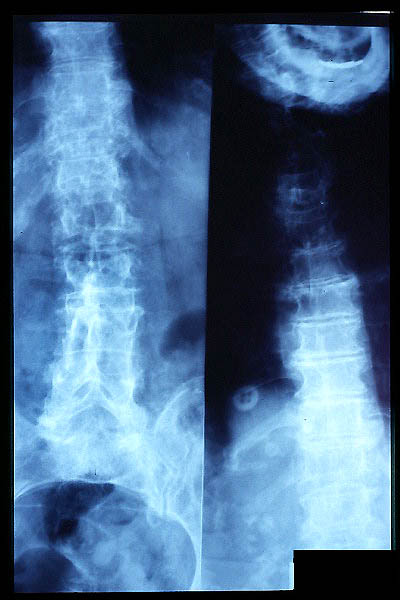

Escoliosis, artrosis, aplastamiento...

Osteoporosis. Cifosis.

Fractura vertebral, aplastamiento

Aplastamiento vertebral. Gas. Osteoporosis.

Aplastamiento vertebral. Osteoporosis.